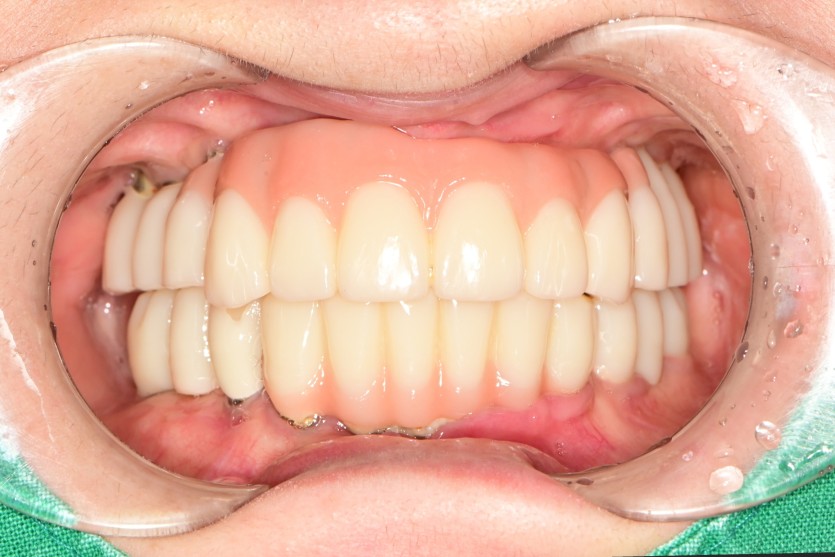

전체 임플란트 증례입니다.

16개의 임플란트로 완성하였습니다.